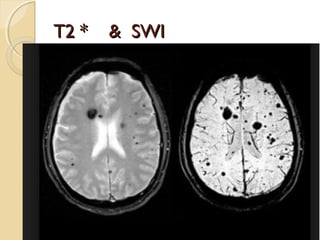

DIFFUSE AXONAL INJURYDIFFUSE AXONAL INJURY

Rarely detected on CT ( 20% of DAI

lesions are hemorrhagic)

MRI:T1,T2,T2 GRE, SWI

DAIDAI

Due to acceleration/deceleration to

whtie matter + hypoxia

Patients have severe LOC at impact

Grade 1: axonal damage in WM only -67%

Grade 2:WM + corpus callosum

(posterior > anterior) – 21%

Grade 3:WM + CC + brainstem

T2 * & SWIT2 * & SWI

DIFFUSE AXONAL INJURYDIFFUSEAXONAL INJURY Rarely detected on CT ( 20% of DAI lesions are hemorrhagic) MRI:T1,T2,T2 GRE, SWI

DAIDAI Due to acceleration/decelerationto whtie matter + hypoxia Patients have severe LOC at impact Grade 1: axonal damage in WM only -67% Grade 2:WM + corpus callosum (posterior > anterior) – 21% Grade 3:WM + CC + brainstem

T2 * &SWIT2 * & SWI